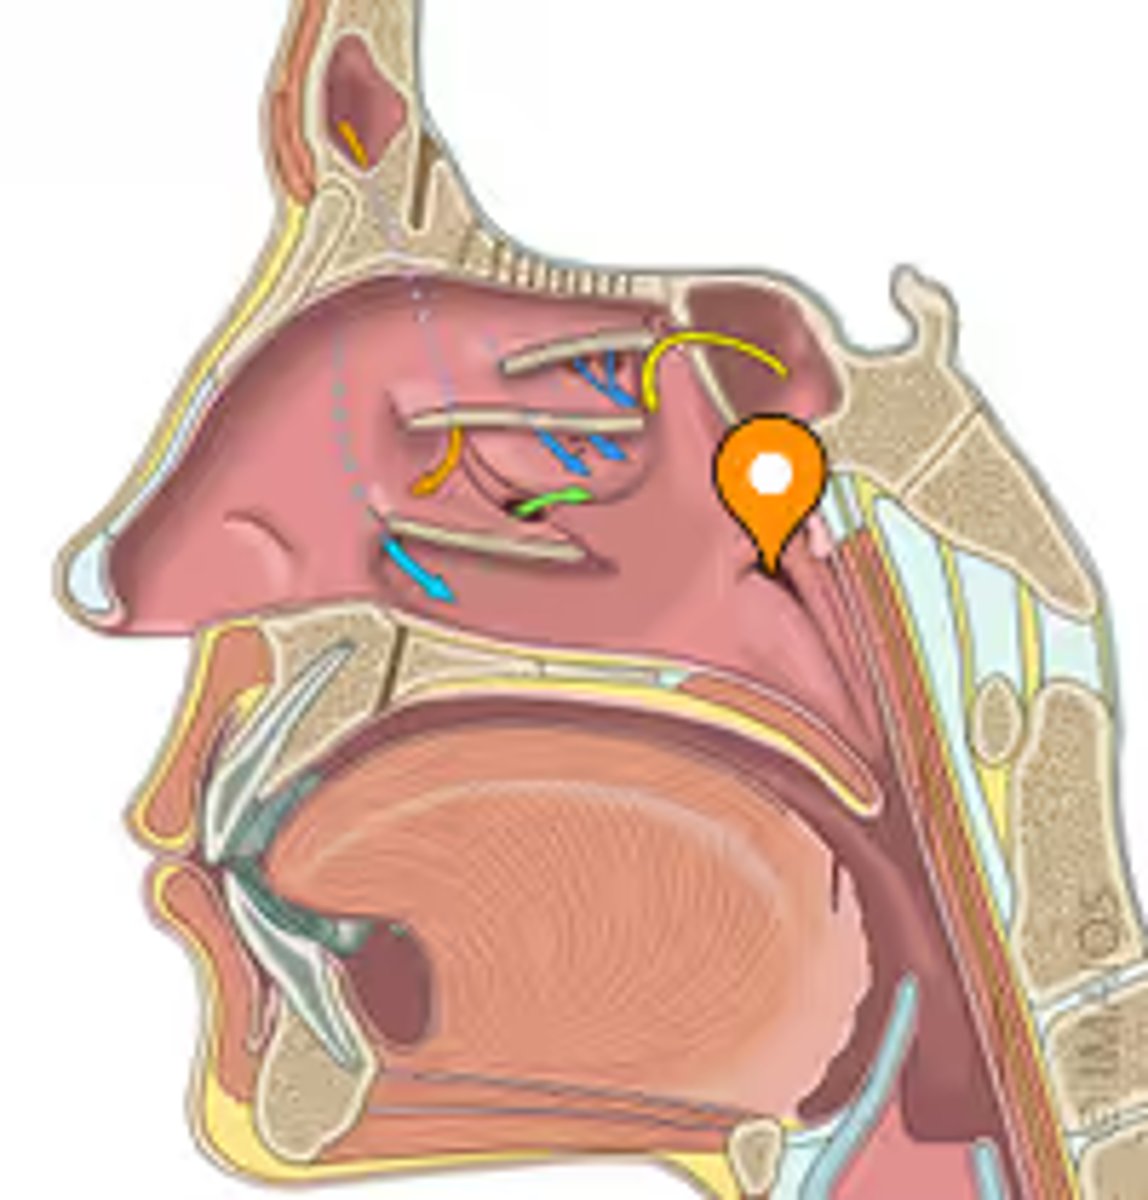

pharyngeal tonsil

tonus tubaris

opening of pharyngotympanic tube

salpingopharyngeal fold

superior meatus

middle meatus

inferior meatus

inferior nasal concha